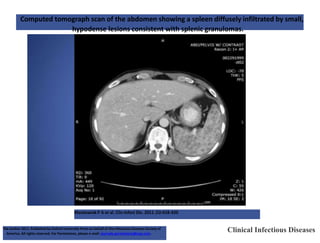

SPLENIC TUBERCULOSIS • Itcan occur due to disseminated or miliary form of the disease • Most commonly encountered in HIV pt(developed countries) • Fever, weight loss, diarrhea, left upper abdominal pain, splenomegaly • Investigations • Image-guided percutaneous needle biopsy is the gold standard for diagnosis. CECT-abdomen-multiple hypo echoic foci(<2cm)

Computed tomograph scanof the abdomen showing a spleen diffusely infiltrated by small, hypodense lesions consistent with splenic granulomas. Mackowiak P A et al. Clin Infect Dis. 2011 ;52:418-420 Clinical Infectious Diseases The Author 2011. Published by Oxford University Press on behalf of the Infectious Diseases Society of America. All rights reserved. For Permissions, please e-mail: journals.permissions@oup.com.